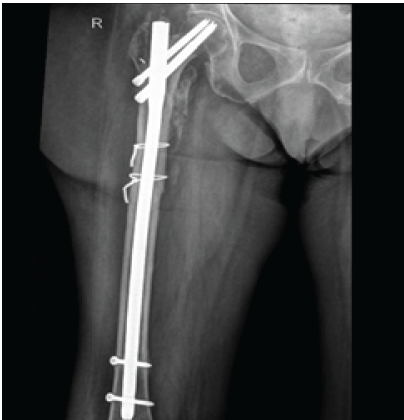

Sutures were removed on post-operative day 15. Regular follow-up at 4 weeks, 2, 3, 6, and 12 months did not show any clinical, biochemical, or radiological signs of infection (Fig. 4 and 5).

Figure 5: Radiologically healed fracture with no signs of infection at 1 year follow-up.